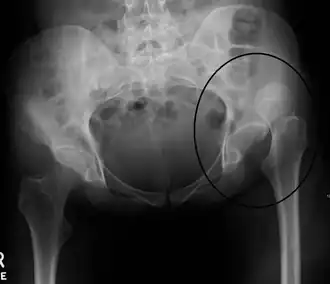

| Radiografia em que se observa deslocação da articulação na anca esquerda | |

Uma luxação da anca (português europeu) ou luxação do quadril (português brasileiro) é uma deslocação da articulação entre o fémur e a bacia.[1] De forma mais específica, é quando a extremidade esférica do fémur se desencaixa do acetábulo da bacia onde está normalmente encaixada.[1] Os sintomas geralmente consistem em dor e incapacidade em mover a anca.[1] Entre as possíveis complicações estão a necrose avascular da anca, lesões no nervo ciático ou artrite.[1]

As luxações são geralmente causadas por traumatismos significativos, como os que resultam de acidentes de viação ou quedas de elevada altura.[1] Em muitos casos ocorrem também outras lesões associadas.[2][6] As luxações da anca podem também ser o resultado de uma substituição da anca ou de uma anomalia do desenvolvimento denominada displasia de desenvolvimento da anca.[7] O diagnóstico é geralmente confirmado com radiografias simples.[2]